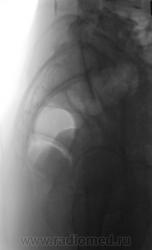

Из анамнеза известно, что примерно 2 месяца тому "летела" со сноутборга около 200 метров. Сейчас беспокоят боли в области спины, крестца и лонного сочленения. УЗИ было сделано всего, что только можно, везде - "норма". Хирурги, вроде-бы тоже ничего не находят. Но боли, видать значительные, походка вынужденная. На рентгенографию была направлена, как жест отчаяния, мол может быть, что-то найдут.

Рентгенограмма в прямой проекции.

1. Не исключаю поперечный перелом S5.

2. Лонное сочленение очевидно,подверглось значительному растяжению (имеется локальный вакуум-феномен слева), умеренно выраженые явления симфизита (опять же - постравматического).

1. По первым снимкам не отпускало впечатление о повреждении левого крестцово-подвздошного сочленения. После подготовки вроде-бы все нормально, но все равно что-то гложет.

2. А на боковой массе крестца справа разве не линия консолидирующегося перелома?